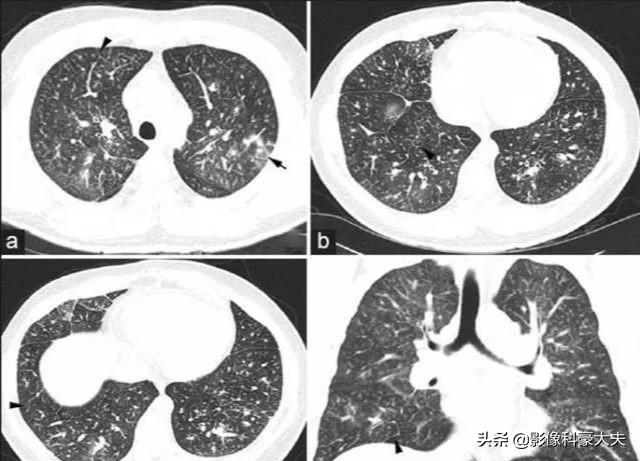

这是一位日本的中年男性病人,确诊胃腺癌6周,因为进行性呼吸困难,呼吸急促入院检查,双肺多发点片状影,这个病人很快死亡了,病理结果是肿瘤血栓性微血管病。这是由于一些转移性的小瘤栓堵塞肺小动脉,并引起一系列病理变化,这种严重的并发症预后差,平均生存期只有9天。

值得庆幸的是,这种严重并发症发病率很低,尸检结果显示,癌症患者该并发症发生率为0.9~3.3%,并且常见于腺癌。

临床上有一些腺癌患者明明是比较早期,却在短时间内死亡,有的可能就是这个原因。